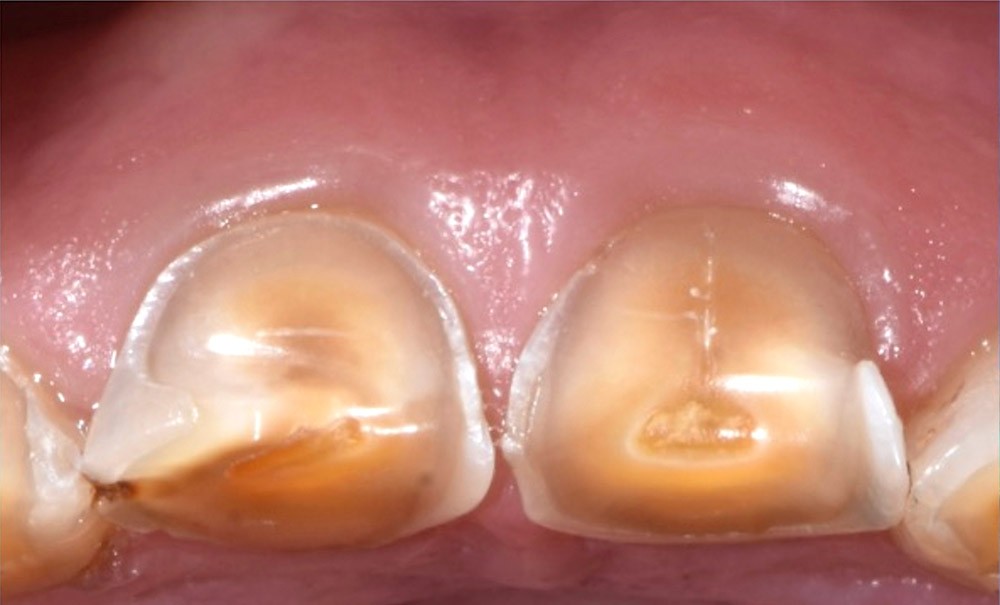

Le cas clinique présenté ici illustre cette démarche thérapeutique. À la suite d’un diagnostic de cancer des voies aérodigestives supérieures, un patient de 68 ans a bénéficié d’un traitement par radiothérapie cervico-faciale, terminée depuis plus de 2 ans. Il souhaite désormais retrouver une réhabilitation fonctionnelle et esthétique de sa cavité orale. Il indique que le délabrement de ses dents antérieures est à l’origine d’un important préjudice esthétique, qui l’a conduit à ne plus sourire. De plus, ses dents absentes réduisent fortement ses capacités masticatoires. Ces différents facteurs influent donc directement son estime de soi et sa qualité de vie, paramètres clés de la rémission dans le cadre oncologique. À l’examen clinique, il présente une perte de calage postérieur, avec des édentements terminaux secteur 2 et 4, ainsi que de volumineuses pertes de substance au niveau des dents présentes (fig. 1).